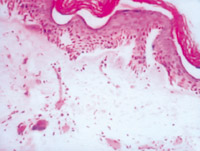

5-2-4 伤后第5天,真皮浅层组织液化性坏死、剥落  HE×100